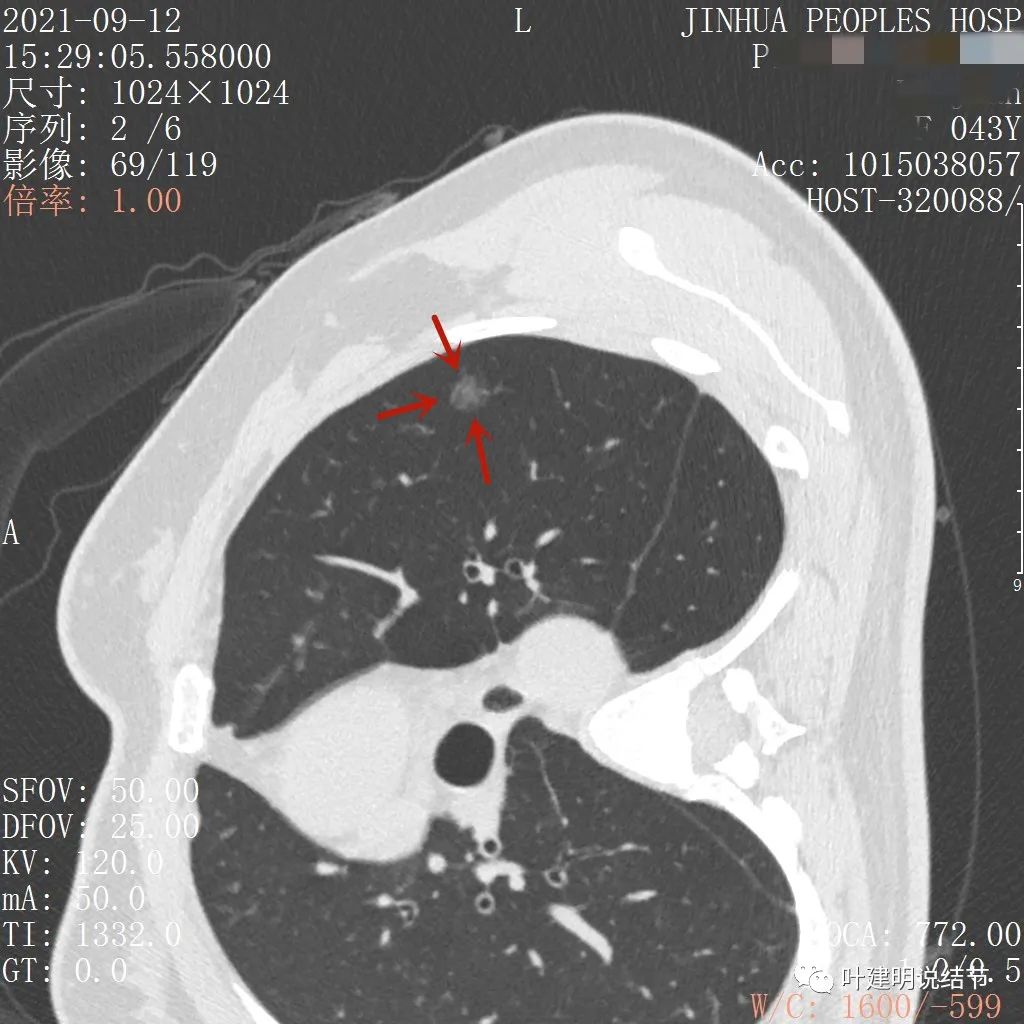

病灶瘤肺边界清,密度偏低,有点散,但有微小血管进入(桔色箭头)

病灶整体密度较低,但轮廓较清,内部密度不大均匀,显得杂乱